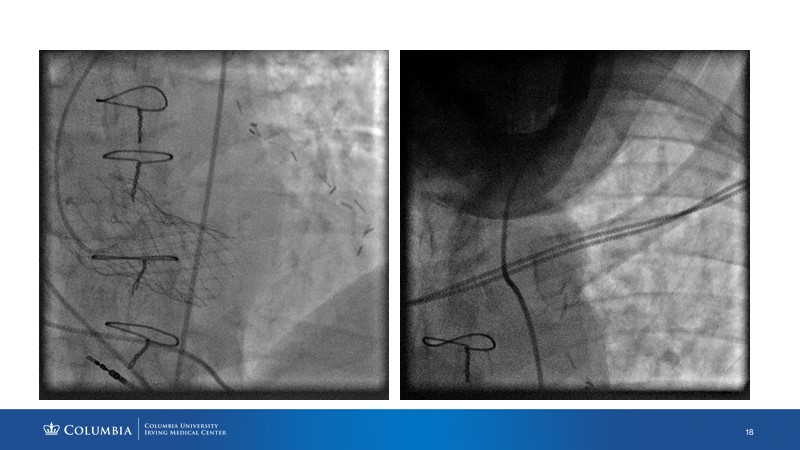

Through the presentation of real-life clinical cases, this session will allow you to discover the use of ALLEGRA for valve-in-valve TAVI, understand the management of coronary artery disease in TAVI patients, better detect when and how to protect coronary arteries during TAVI, or even learn how to perform commissural alignment with ALLEGRA.

- To better detect when and how to protect the coronary arteries during TAVI